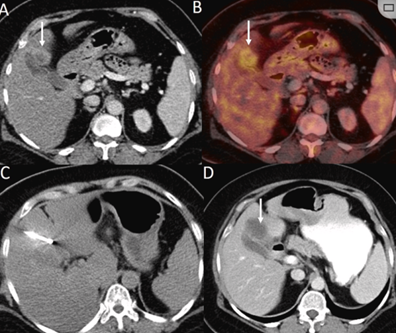

(A)动脉期CT图像显示有一个包膜下结节(箭头)。(C) 在手术过程中的CT显示一个冷冻探针位于病灶内。随访时间中位数为7个月(范围:3-12个月),随访期间患者无局部肿瘤进展或死亡。

(A)门静脉期 CT 图像显示胆囊附近有病变(箭头)。(D)消融手术后 1 个月CT 显示完全消融。

本研究中患者随访期间无局部肿瘤进展,无死亡病例,没有发现与手术相关的并发症。证实冷冻消融是一种有效的治疗方式,在技术上是可行和安全的。由于肝包膜下病变位置特殊,射频消融有出血及肿瘤种植的风险,可能会对邻近器官造成损伤,并且增加局部肿瘤进展的风险。近年来,冷冻消融术的应用逐渐广泛,有研究显示冷冻消融治疗具有明显优势,可治疗特殊部位的肝肿瘤。本研究的目的是评价冷冻消融治疗肝包膜下肿瘤的安全性和有效性。回顾性纳入2016年7月1日至2018年9月1日期间冷冻消融的57例患者。包括42例男性和15例女性,平均年龄为62.4岁(范围:48-82岁)。每个患者有1个或2个平均肿瘤尺寸为2.4cm的病变(范围:0.6-4.0cm)。所有患者均患有慢性肝病或肝硬化,并伴有乙型肝炎(n=52)、丙型肝炎(n=3)和其他肝炎(n=2)。根据肿瘤位置,在膈肌或肝脏下附近有18个病变(26.5%),胃或肠附近有9个病变(13.2%),腹壁附近有33个病变(48.5%),肾脏附近有8个病变(11.8%)。